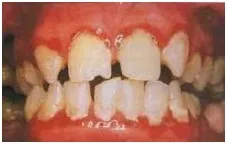

ژنژیویت مزمن یا التهاب لثه: در بچه ها شایع می باشد. لثه ها قرمز و متورم هستند و به راحتی خونریزی می کنند. اغلب این حالت به دلیل عدم رعایت بهداشت دهان می باشد که با مراقبت های دندانپزشکی مثل جرمگیری و برساژ دندان و نیز رعایت بهداشت مثل استفاده صحیح از مسواک و نخ دندان قابل درمان و پیشگیری است. گاهی اوقات نیز تنفس دهانی و یا شروع دوره بلوغ، لثه را مستعد التهاب می نمایند.

پریودنتیت مهاجم منتشر(جنرالیزه): ممکن است در زمان بلوغ شروع شود وکل دهان را گرفتار کند. همراه با التهاب لثه وتجمع فراوان جرم می باشد.منجر به از دست رفتن بافت های نگهدارنده دندان می شود. در رادیو گرافی(عکس از دندان) تحلیل استخوان دیده می شود.این بیماری معمولا زمینه ارثی دارد.

علائم بیماری پریودنتال یا بافت های نگهدارنده دندان: خونریزی لثه، تورم لثه، تحلیل لثه، بوی بد دهان و تحلیل استخوان که در رادیو گرافی دیده می شود.